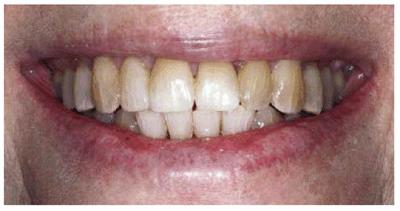

Goldstein cited the revolutionary concept that esthetic dentistry is, in fact, a health service.6 During the last decade, older adults who elected to have treatments that involved all esthetic disciplines embraced this concept of oral health. A good example of an older adult undergoing extensive esthetic dental treatment appears in Figures 29-1A to C 29-1D to F 29-1G 29-1H 29-1I and J 29-1K 29-1L 29-1M 29-1N, and 29-1O

Figure 29-1A to C: This 76-year-old lady presented for treatment after a lifetime of dissatisfaction with her crowded teeth.

Figure 29-1G: After the removal of the orthodontic appliances, the teeth are much straighter but still discolored.

Figure 29-1H: After restorative treatment featuring tooth- colored restorations and bleaching, the patient has the smile she has always wanted.